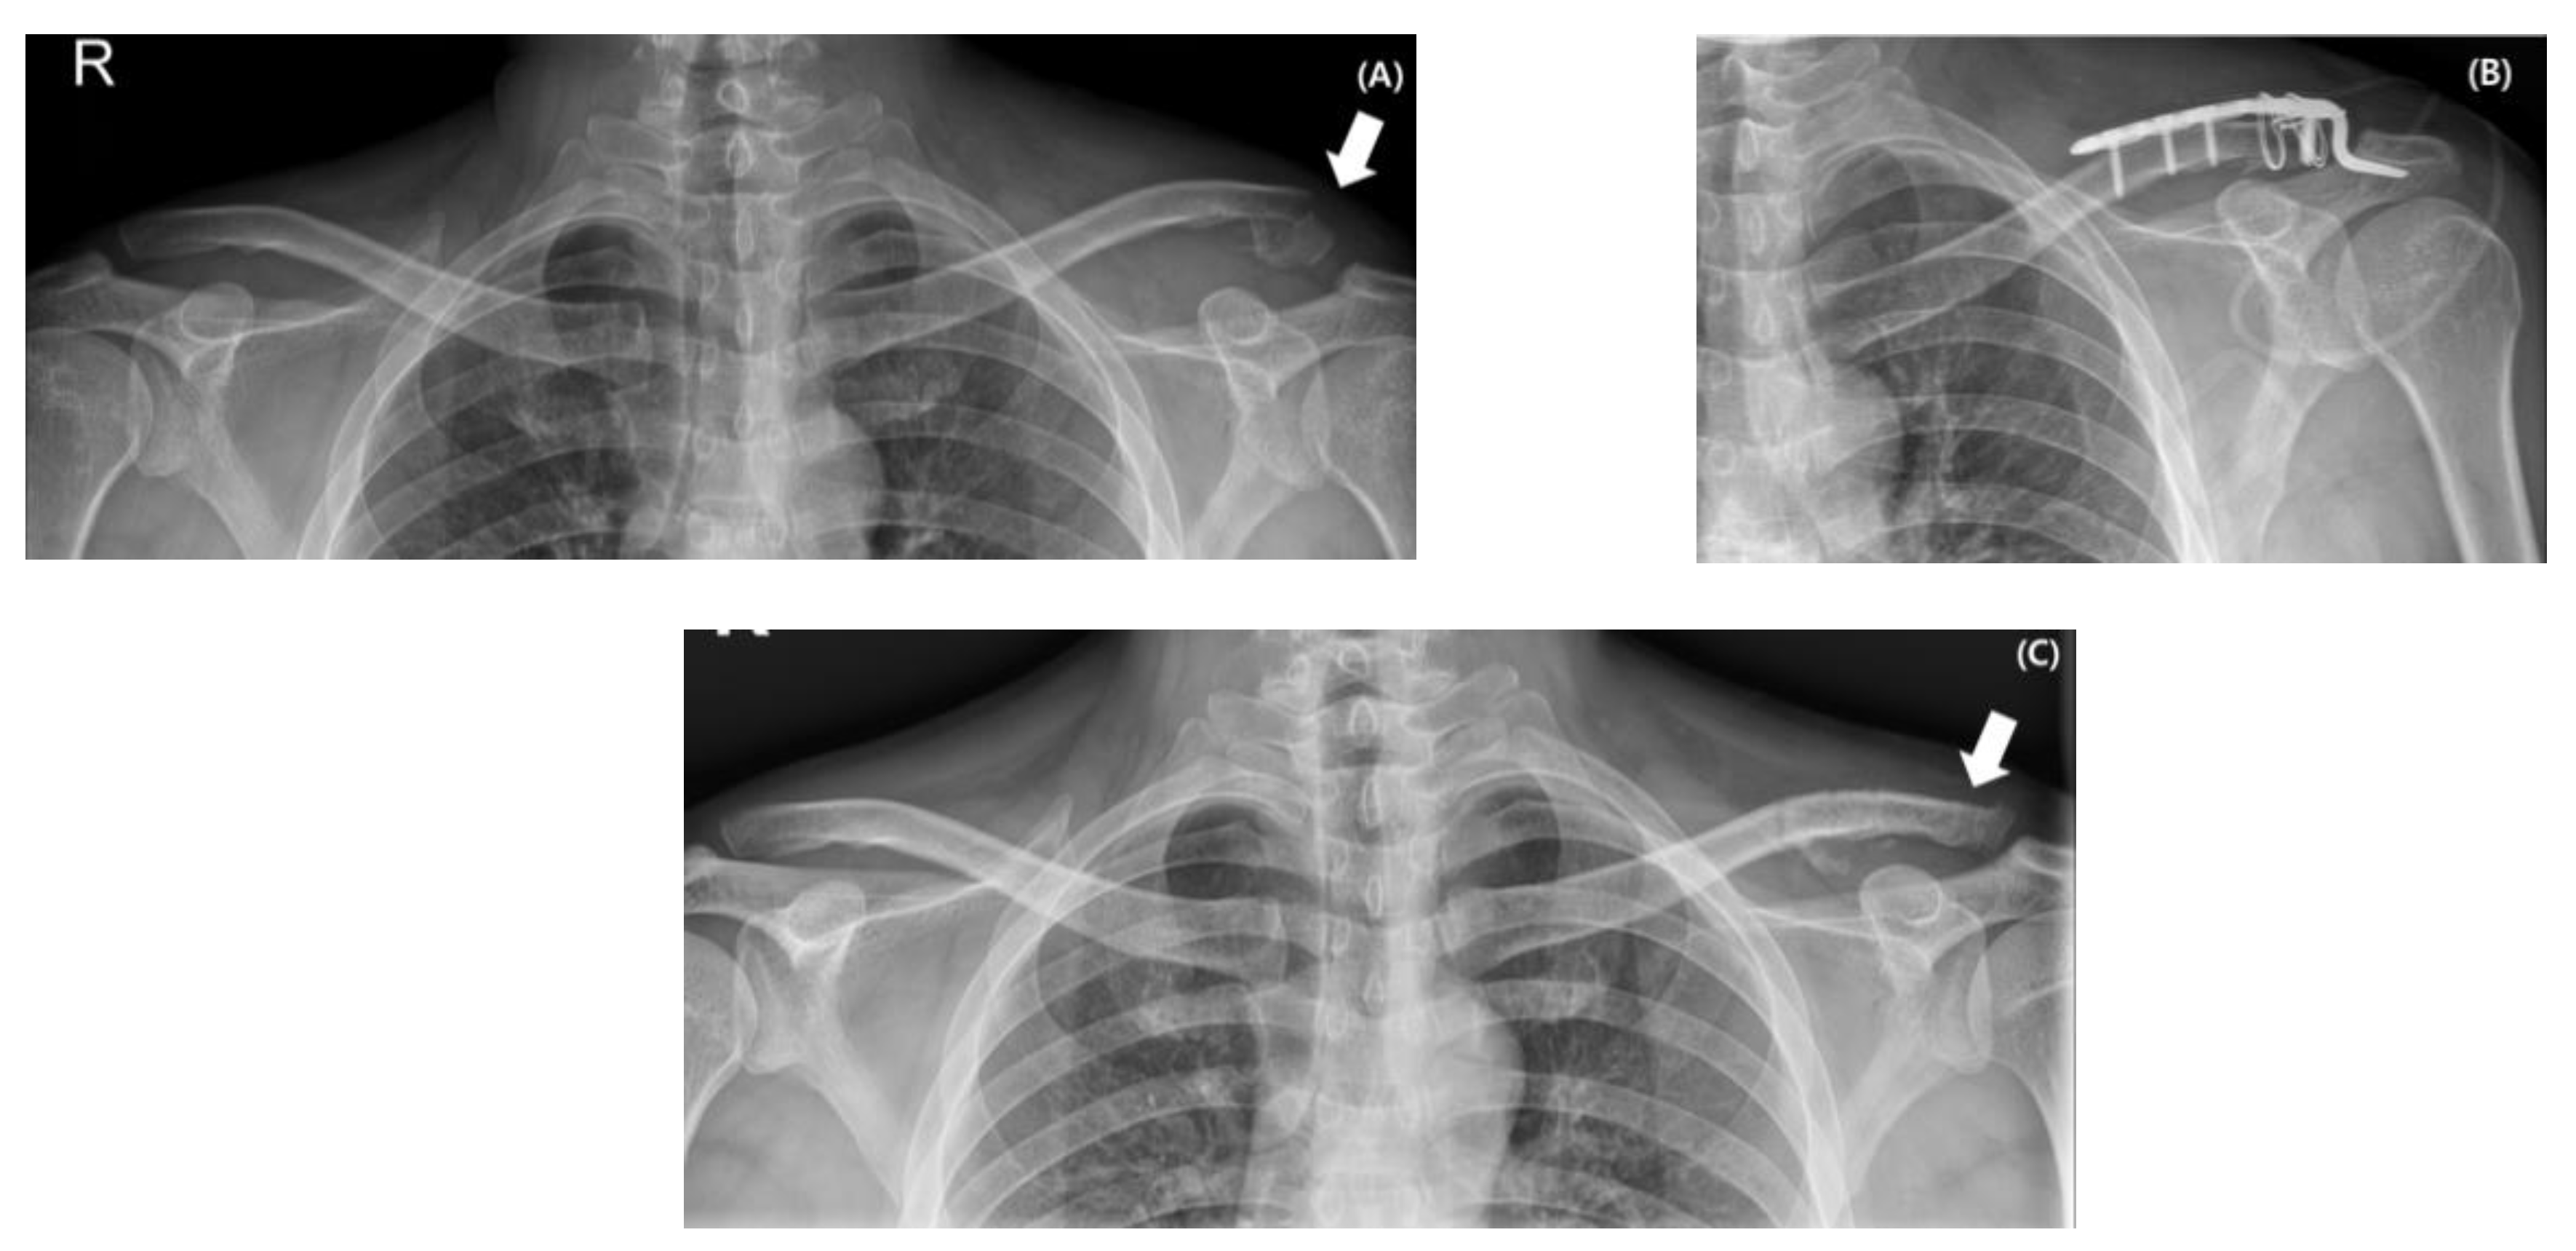

2.2. Surgical Procedures